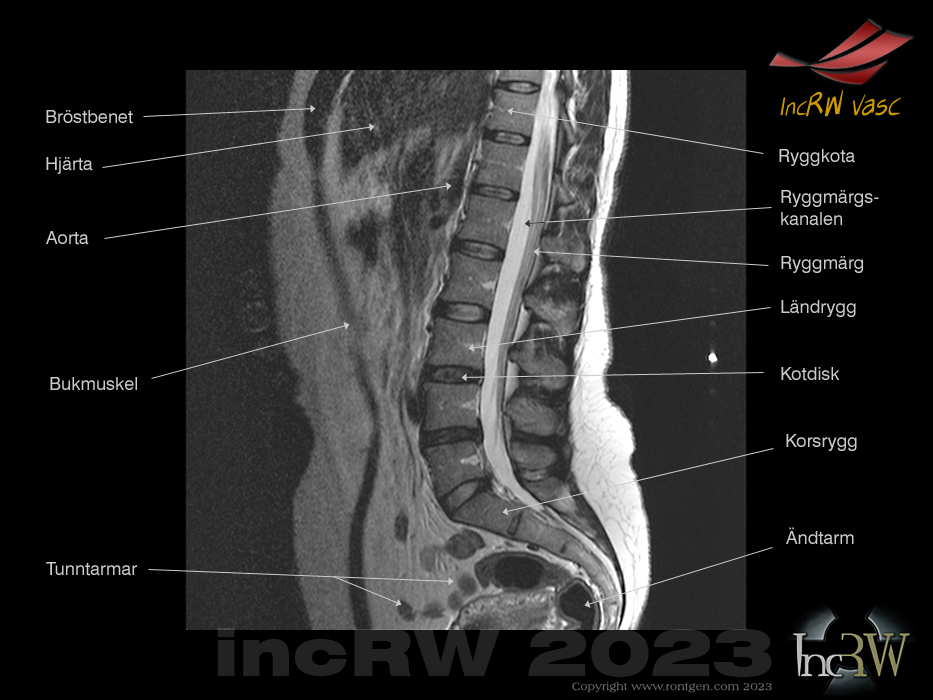

En MR-undersökning ställs in så att den ger optimala bilder av det organområde som remittenten anger i sin remiss till röntgenavdelningen där misstänkt patologi kan finnas dvs. ge bra bilder av skelettet eller mjukdelar eller blodkärl, etc.

Visst ser man andra kroppsliga strukturer i MR-bilderna men dessa blir oftast inte optimalt avbildade utan kan enbart ge en grov bedömning och i många fall medger ingen som helst ytterligare bedömning. Detta gäller framför allt organ som rör på sig vid bildtagningen såsom lungor samt stora delar av buken som kan ge stora artefakter (bildstörningar) ism. andning och tarmrörelser.

Jämfört med datortomografi (CT) där stora delar av kroppen ofta kommer med på bildtagningen beroende på kroppsavsnittet som avbildas. Dessa övriga avbildade organ som kommer med på CT-bilderna blir ofta så pass bra att man lätt kan ställa en diagnos på bifynd trotts att patienten kommer för att undersöka ett annat specifikt organ och problemområde. Dagens snabba CT-maskiner skannar igenom en hel kroppsvolym på några få sekunder vilket oftast ger bra bilder oavsett om man håller andan eller inte.